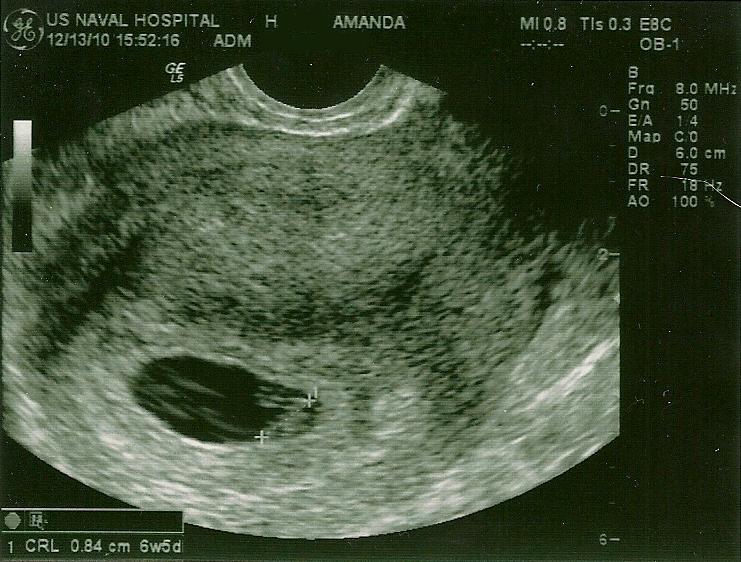

Babies babies! We got to see them again today... with pictures this time!

This one shows both of the sacs together-you can't see the babies because of the angle, but you can see that there are indeed two in there and the ultrasound machine wasn't playing tricks on us!

We thought it was soooo hilarious when the doc checked for triplets (you can sense the sarcasm right?) ...it was a really good visit, a lot of our basic questions were answered. I was put on extra iron and extra folic acid, and put on Zofran for the nausea instead of the Benadryl. I'm still nervous, since having multiples puts us at higher risk for miscarriage. I'll be super glad when the first trimester is over. Only 40 days to go!

Next appointment is about 2 1/2 weeks from now-which was supposed to be my "initial visit". I'll get another ultrasound then! I'll be sent for Level 2 ultrasounds in Charleston or Savannah every so often to check growth and progress more thoroughly, not sure when they start or how often I'll go. I'm excited to be able to see these little babes more often!

Baby A was measuring 6w5d (right on track, as both of them were measuring 6w3d Friday night) and had a heartbeat of 145bpm.